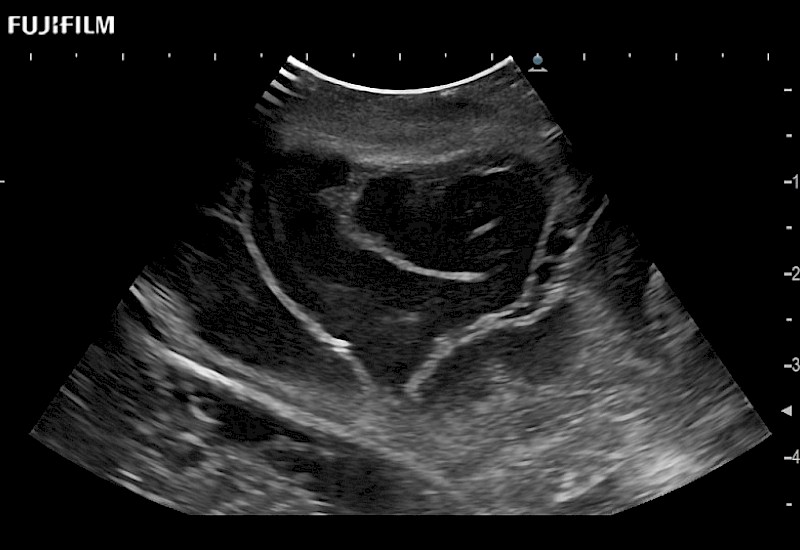

Tight curved (12mm) array transducer that is ideal for scanning during cranial guidance procedures.

Smaller footprint (20mm) curved array transducer that is ideal for scanning during cranial guidance procedures.